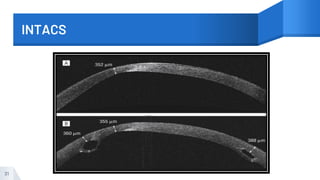

INTACS

Intrastromal Corneal Ring Segments

30 Picture Courtesy: https://www.allaboutvision.com/conditions/inserts.htm